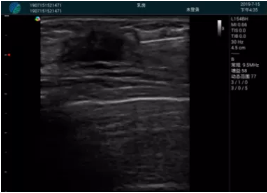

可視化穿刺引導(dǎo)

M20實(shí)時(shí)引導(dǎo):向包塊后方間隙注射利多卡因

清晰顯示腺體內(nèi)低回聲快影,邊界清晰,包膜較光滑

確定進(jìn)針路徑并實(shí)時(shí)監(jiān)測(cè)抽吸針與腫塊位置關(guān)系

抽吸針進(jìn)入腫塊內(nèi)部進(jìn)行旋切

抽吸過程中可見腫塊明顯縮小,并根據(jù)腫塊位置改變針道位置

抽吸旋切后再進(jìn)行超聲復(fù)查,原腫塊區(qū)域未見殘留組織及出血

超聲引導(dǎo)下抽吸旋切取出的腫塊組織